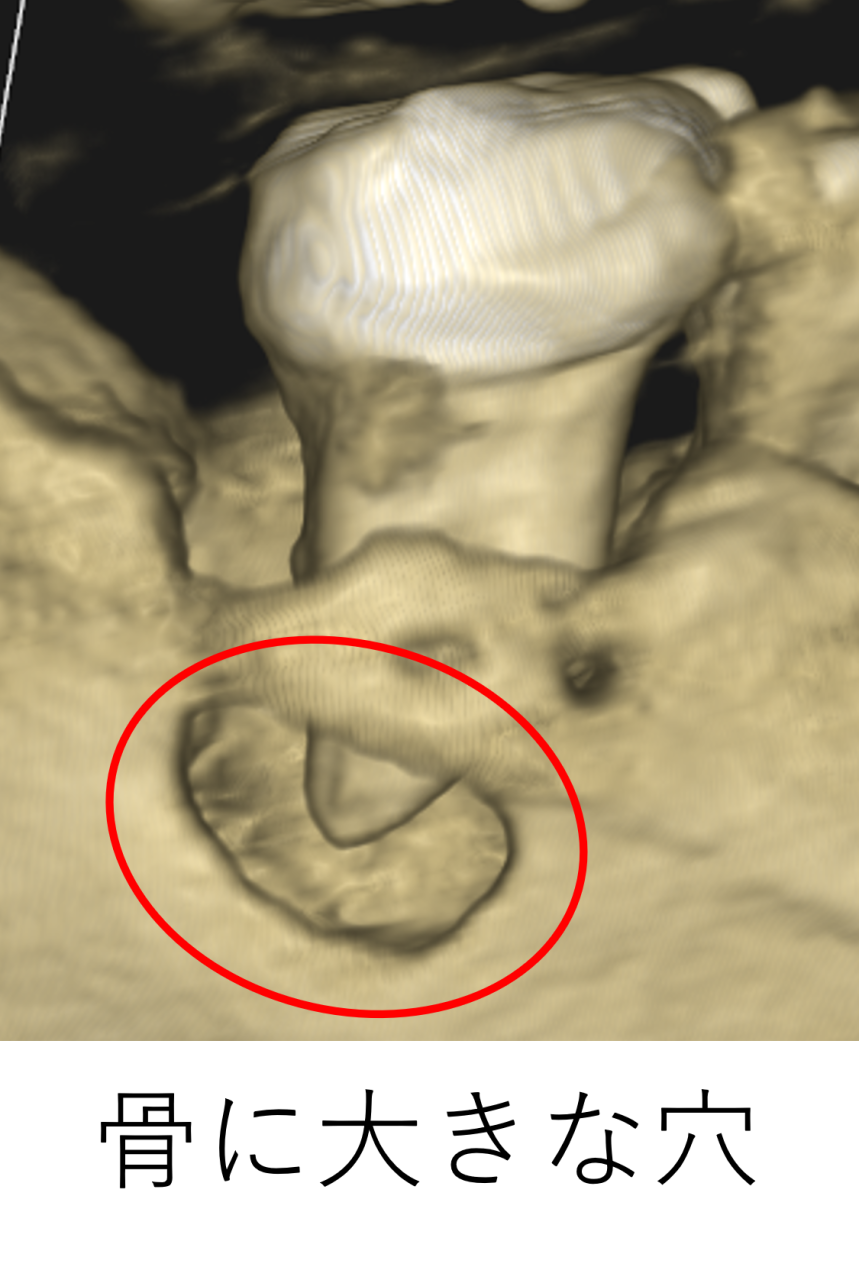

精密に検査するため、CTを撮影した所、予想以上に大きな病気で骨が溶けてしまっていることが分かりました。特に内側の骨が完全に貫通し、大きな穴があいています。これでは抜いた方が良いと言われても無理はありません。